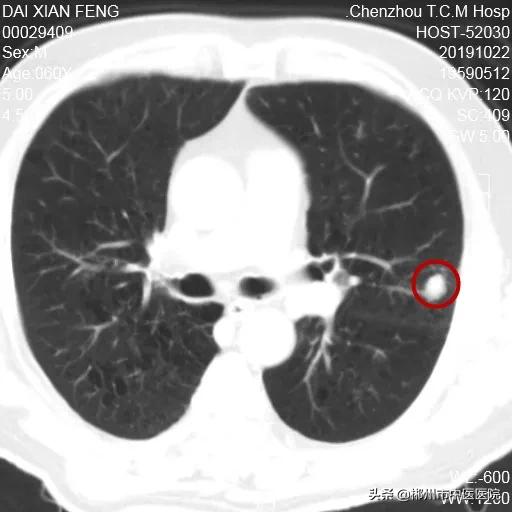

2019年10月住院期间发现左肺占位

陀螺刀治疗前病灶大小15.3X12.4mm